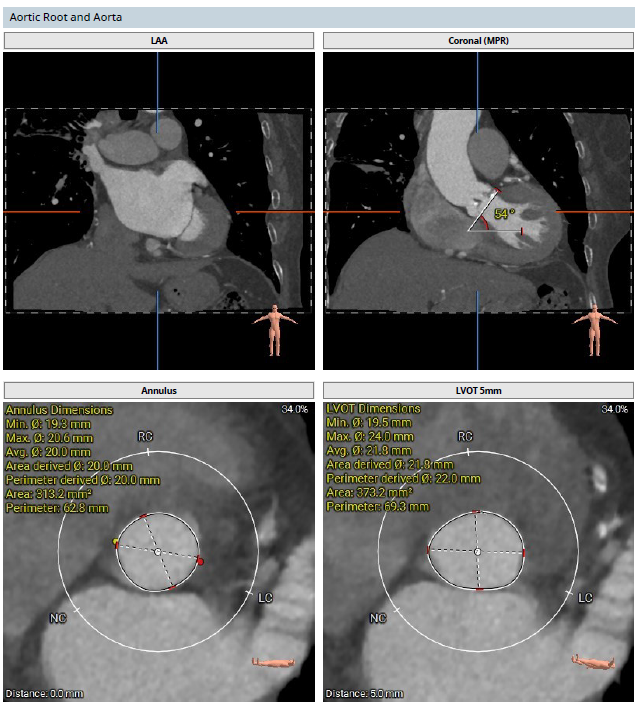

该患者术前CT分析瓣环20.0mm,流出道22.0mm, Type0型二叶瓣,瓣叶轻中度钙化并增厚,瓣膜锚定力可,流出道直筒偏敞口,预估瓣膜释放后位移风险低,少量瓣周漏可能;

冠脉开口高度可,右冠瓣冗长瓣叶,预估冠脉阻挡风险低术中密切关注冠脉血流灌注,必要时冠脉保护;

预计右股主入路,股动脉分叉略高,注意穿刺点位置,18mm球囊预扩,植入TaurusElite AV23瓣膜,瓣膜释放到工作位后多体位充分评估瓣膜位置及形态情况,结合超声结果,确认无误再行释放,必要时瓣中瓣处理。